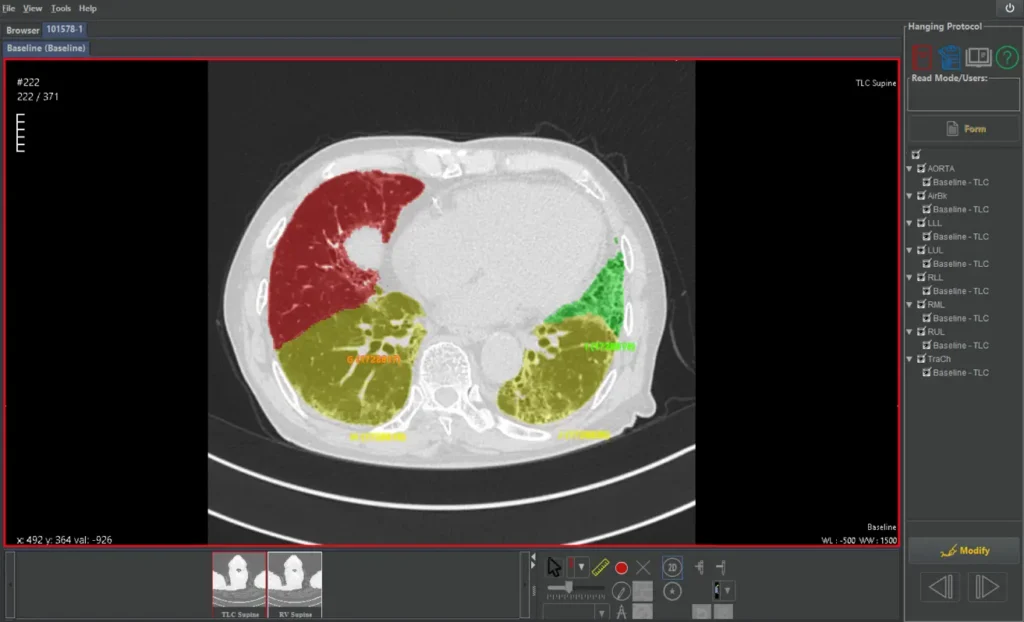

Automated lobe segmentation enables precise, region-specific quantification for advanced metrics such as QILD, QLF, and air trapping.

Quantitative Image Analysis (QIA) combine proprietary denoising with CT-based quantification of fibrotic lung disease, including lung volume and QILD metrics, to support precise, pattern-based evaluation of interstitial scarring.